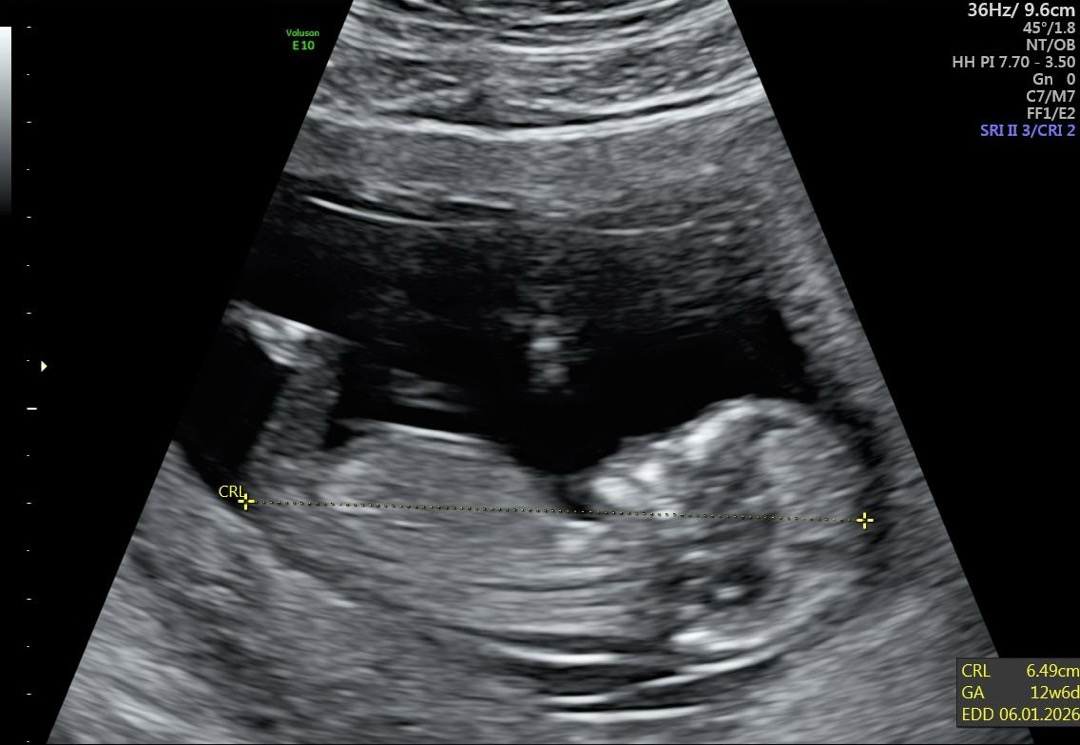

안녕하세요 12주 6일차에 찍은 초음파 인데 성별 봐주시면 감사하겠습니다 :D